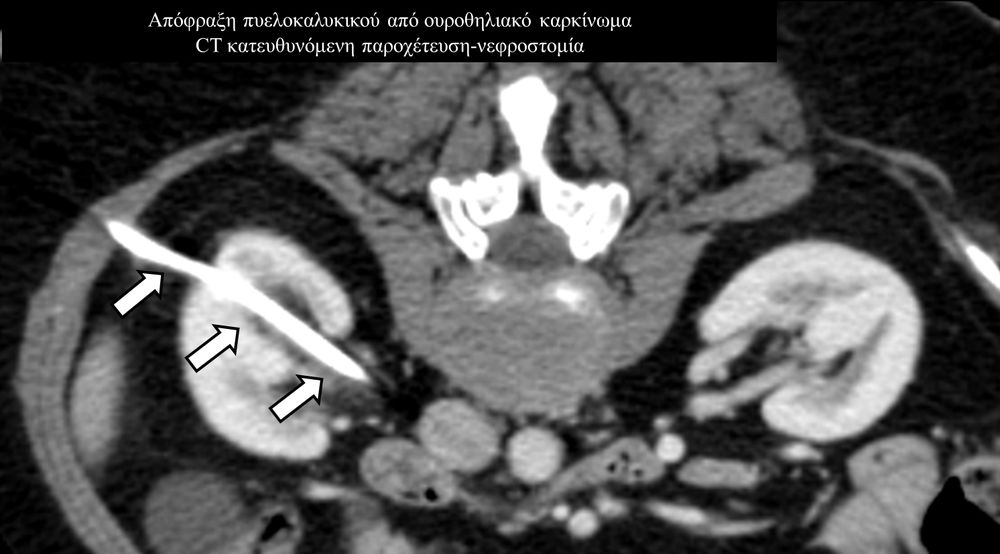

Η παρέμβαση διενεργείται υπό την καθοδήγηση αξονικού τομογράφου ή υπερήχων ή και με συνδυασμό τους. Ο επεμβατικός ακτινολόγος αρχικά αναισθητοποιεί την ανατομική περιοχή ενδιαφέροντος με τη χρήση τοπικής αναισθησίας και παρακεντεί την συλλογή διαδερμικά με λεπτή βελόνη. Στη συνέχεια μέσω ομοαξονικών συστημάτων συρμάτων-καθετήρων-διαστολέωντοποθετείται διαδερμικός καθετήρας τύπου pig-tail εντός της συλλογής, ο οποίος συνδέεται με εξωτερική παροχέτευση.